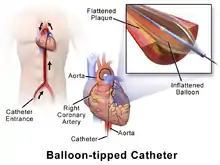

Angioplasty, also known as balloon angioplasty and percutaneous transluminal angioplasty (PTA), is a minimally invasive endovascular procedure used to widen narrowed or obstructed arteries or veins, typically to treat arterial atherosclerosis.[1] A deflated balloon attached to a catheter (a balloon catheter) is passed over a guide-wire into the narrowed vessel and then inflated to a fixed size.[1] The balloon forces expansion of the blood vessel and the surrounding muscular wall, allowing an improved blood flow.[1] A stent may be inserted at the time of ballooning to ensure the vessel remains open, and the balloon is then deflated and withdrawn.[2] Angioplasty has come to include all manner of vascular interventions that are typically performed percutaneously.

A coronary angioplasty is a therapeutic procedure to treat the stenotic (narrowed) coronary arteries of the heart found in coronary heart disease.[1] These stenotic segments of the coronary arteries arise due to the buildup of cholesterol-laden plaques that form in a condition known as atherosclerosis.[3] A percutaneous coronary intervention (PCI), or coronary angioplasty with stenting, is a non-surgical procedure used to improve the blood flow to the heart.[1]

Access to the vascular system is typically gained percutaneously (through the skin, without a large surgical incision). An introducer sheath is inserted into the blood vessel via the Seldinger technique.[17] Fluoroscopic guidance uses magnetic resonance or X-ray fluoroscopy and radiopaque contrast dye to guide angled wires and catheters to the region of the body to be treated in real time.[18] Tapered guidewire is chosen for small occlusion, followed by intermediate type guidewires for tortuous arteries and difficulty passing through extremely narrow channels, and stiff wires for hard, dense, and blunt occlusions.[19] To treat a narrowing in a blood vessel, a wire is passed through the stenosis in the vessel and a balloon on a catheter is passed over the wire and into the desired position.[20] The positioning is verified by fluoroscopy and the balloon is inflated using water mixed with contrast dye to 75 to 500 times normal blood pressure (6 to 20 atmospheres), with most coronary angioplasties requiring less than 10 atmospheres.[21] A stent may or may not also be placed.